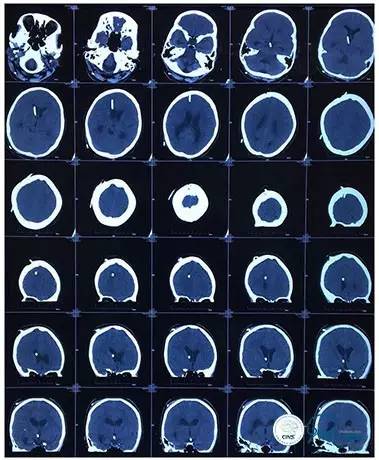

头颅CT

头颅CT(2017.6.20)

颞骨CT(2017.6.20)

2016-06-03 CT

2017-06-07 CT

术后头颅CT